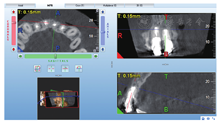

根尖约4 mm×3 mm透影区,根尖部唇侧骨板缺损。

根尖可见约1 mm×2 mm透影区,唇侧骨板完整(图4)。

根尖未见明显低密度影。1年前根尖X线片显示

根充欠填,根尖低密度影,

牙冠完整,根尖无异常(图5)。

龈缘下方约5 mm扇形水平切口,翻起黏骨膜瓣,可见

根尖区骨质缺损,搔刮肉芽组织,切除根尖约2 mm。

根尖未见明显骨质缺损,去骨,搔刮肉芽组织,切除根尖约3 mm。对根尖行亚甲蓝染色,显微镜下观察未见明显裂纹。超声工作尖进行根管倒预备,三氧化矿物凝聚体(mineral trioxide aggregate,MTA)(Dentsply,美国)倒充填。组织瓣复位,6-0号线缝合,1周拆线。治疗过程见图6。

显微根尖手术再治疗过程 A:龈缘下方扇形水平切口,翻开组织瓣;B:

根尖切除后;C:使用三氧化矿物凝聚体根尖倒充填后检查;D:手术切口缝合

根尖切除后;C:使用三氧化矿物凝聚体根尖倒充填后检查;D:手术切口缝合术后根尖X线片显示

根充糊剂少量超填,

根充恰填,

倒充填根尖3 mm致密,与桩核末端之间尚有部分空隙(图7)。